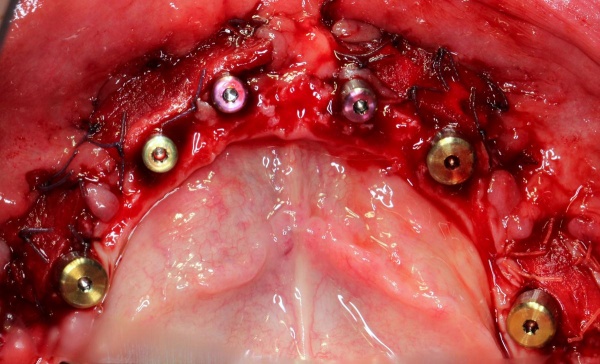

Im August 2012 erfolgten die 3D-gestützte Implantation (6 Implantate, Firma Nobel Biocare, System Active) im Oberkiefer mit Bone Split sowie eine An- und Auflagerungsosteoplastik vom linken Beckenkamm im Unterkiefer nach Entfernung der Miniimplantate (Abb. 3). Nach komplikationsloser Einheilung wurde im Dezember 2012 die Materialentfernung und Implantation im Unterkiefer (6 Implantate, Firma Nobel Biocare, System Active) durchgeführt (Abb. 4). Die Osseointegration verlief ungestört. Aufgrund der ungenügenden Weichgewebssituation im Unterkiefer erfolgte an jedem Implantat bei Freilegung eine Vestibulumplastik mit Einlagerung einer bioresorbierbaren Membran (Firma Botiss, Mucoderm, Abb. 5 und 6). Die endgültige prothetische Versorgung erfolgte durch den truppenzahnärztlichen Kollegen in der Stammeinheit des Patienten (Zahnarztgruppe Nordholz / SanZ Celle) mit einer gaumenfreien implantatgetragenen Teleskopprothese im Ober- und Unterkiefer, die eine festsitzend-herausnehmbare vollständige stomatognathe Rehabilitation des Patienten ermöglichte (Abb. 7 und 8). Er wurde zum halbjährlichen Recall angehalten.